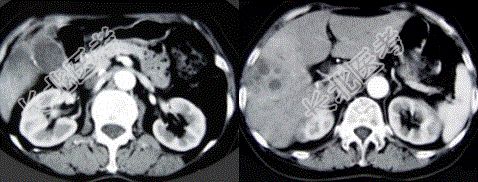

- 单项选择题女性,66岁。右上腹痛, 发热伴有黄疸2个月余,消瘦、纳差, 影像表现如图所示,最可能的诊断是

A、胆囊结石及脂肪肝

B、胆囊结石及肝血管瘤

C、胆囊癌肝转移

D、肝内胆管细胞癌

E、胆囊癌及原发性肝癌